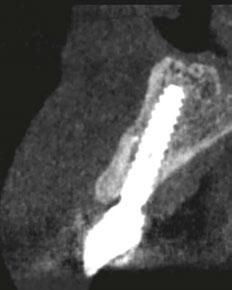

–Implante inmediato en incisivo lateral superior con técnica de «Socket Shield» y acceso vestibular para legrado de la lesión periapical, por el Dr. Ignacio Tormo Jiménez y cols. [106]

Planificación digital y cirugía guiada para dummies. Cómo confeccionar una guía quirúrgica de un modo predecible, por el Dr. Giuliano Fragola.

–Planificación de cirugía guiada de implantes con sistema de guía quirúrgica sin anillas metálicas: a propósito de un caso clínico, por el Dr. Antonio García Sanz y cols. [64]